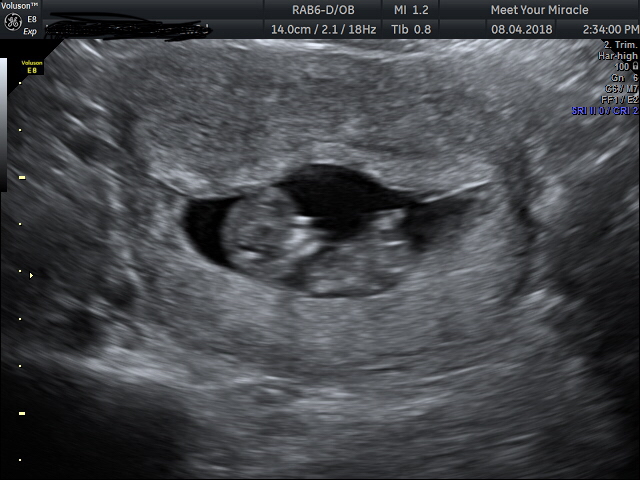

Hi Any gender guesses guys?13 plus 2

Thanks xxx

Hard to say if the stacking is actually a penis or part of the leg in the background..